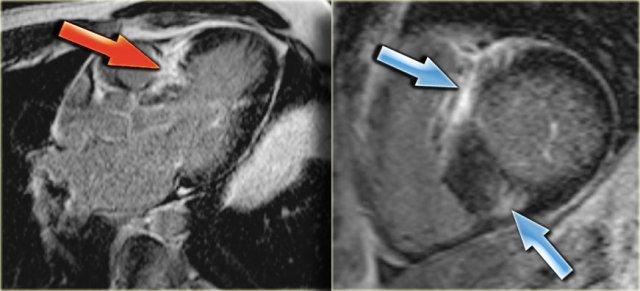

Trái: Hình ảnh ngấm thuốc muộn góc nhìn 3 buồng cho thấy sự ngấm thuốc của vách liên thất nền phì đại (mũi tên)

HOCM (3)

Ở ngoài cùng bên trái là hình ảnh ngấm thuốc muộn góc nhìn 3 buồng, minh họa rõ ràng sự ngấm thuốc của vách liên thất nền phì đại (mũi tên).

Bên cạnh đó là hình ảnh ngấm thuốc muộn trục ngắn cho thấy sự ngấm thuốc điển hình tại các điểm bám của thất phải ở phía trước và phía sau (các mũi tên).

Hình ảnh ngấm thuốc muộn góc nhìn 3 buồng trước (trái) và sau (phải) đốt cồn. Lưu ý nhồi máu xuyên thành của vách liên thất nền (mũi tên).

Điều trị HOCM bao gồm điều trị nội khoa, phẫu thuật cắt cơ tim hoặc đốt cồn [15].

Kết quả của đốt cồn được mô tả rất rõ ràng trên MRI [19].

Bên trái là hình ảnh ngấm thuốc muộn góc nhìn 3 buồng trước và sau đốt cồn.

Lưu ý nhồi máu xuyên thành của vách liên thất nền (mũi tên).